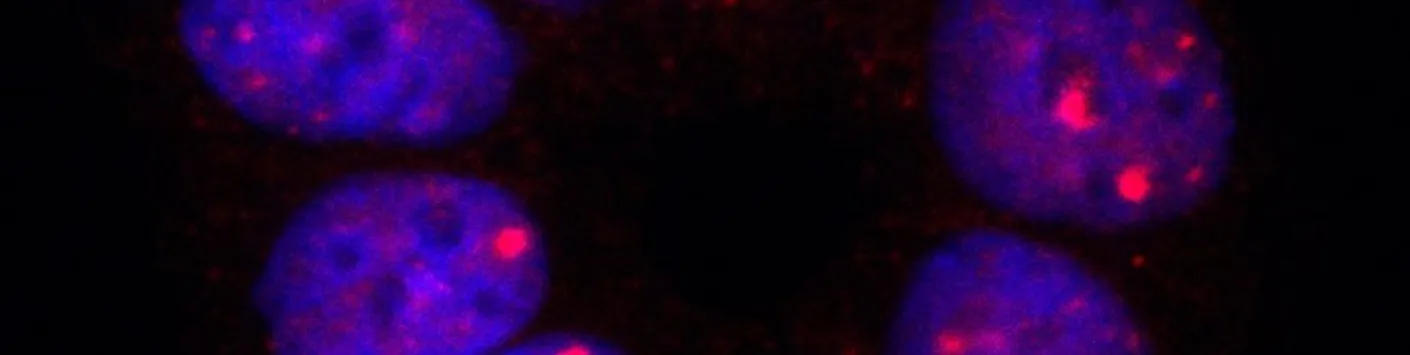

Publication aujourd'hui dans Nature Communications de l'équipe de Alain Chariot, Directeur de recherches FNRS ULiège (GIGA-Stem Cells) et investigateur Welbio-FNRS Télévie, annonçant l'identification de la protéine RNF113A comme nouvelle cible pour le traitement des tumeurs du poumon.

Les cancers du poumon restent très difficiles à soigner en raison d’un diagnostic souvent trop tardif mais aussi parce que les patients développent des résistances aux traitements. Un moyen de contourner ces résistances est d’administrer une combinaison de thérapies. Cette approche nécessite néanmoins que de nombreuses cibles thérapeutiques soient définies pour arriver à traiter ces tumeurs pulmonaires. Cette étude a défini la protéine RNF113A comme nouvelle cible pour le traitement des tumeurs du poumon. https://lnkd.in/gp-Fsr3